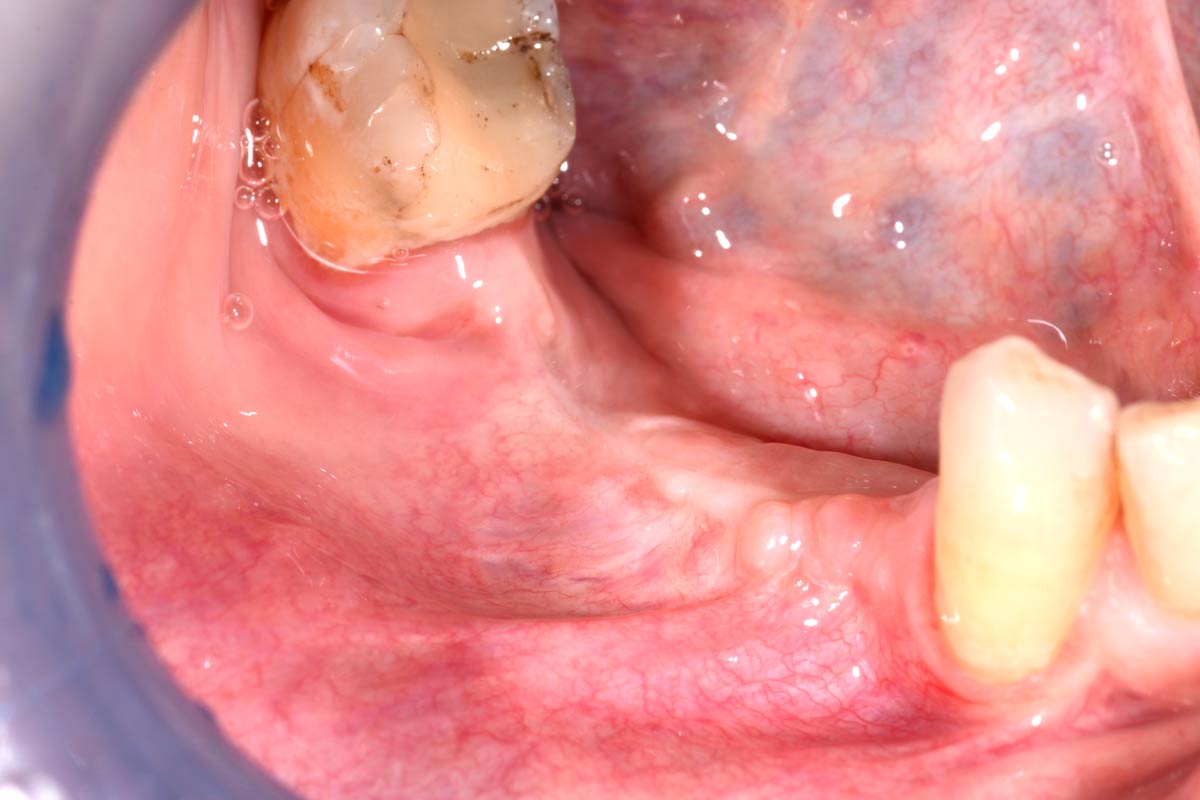

01/29 - Initial clinical situation with pronounced vertical and horizontal bone defectVertical bone augmentation and broadening of attached gingiva using cerabone®, permamem® and mucoderm® - Dr. R. Naimoli

Initial clinical situation with pronounced vertical and horizontal bone defect